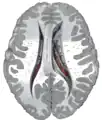

Transverse Cut of Brain (Horizontal Section), basal ganglia is blue

This is a transverse view of the caudate nucleus from a structural MR image.

Transverse view of the caudate nucleus from a structural MR image